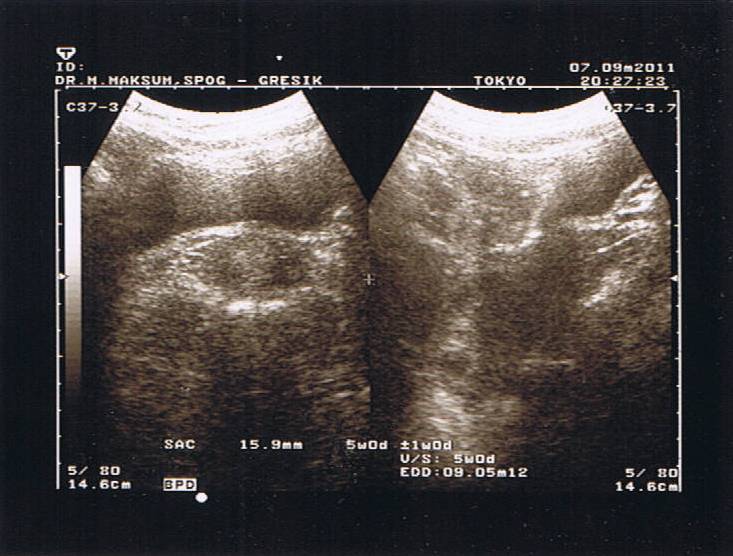

"KARNA ITU IBU BEGITU MULIA" yah, benar sekali, kata2 itu yg sering muncul dlm benak mam, karna dari bulan ke 2, mam merasakan trimester pertama yg begitu berat, benar2 mam rasakan sendiri perjuangan seorang ibu saat mengandung, mual, muntah, g' enak makan, g' enak tidur, g' enak segalanya, bener2 sebuah perjuangan, sampai2 mam pernah berpikir, "mam sudah g' kuat lagi kalau spt ini terus" tp mam, kembali bersemangat saat liat usg si kecil, & kembali berfikir, setelah penantian hampir 1 tahun, do'a mam terjawab dan ini adalah anugrah terindah dari Tuhan yg harus di perjuangkan, mam pun kembali kuat dan tentu dengan pap yang selalu ada mendampingi mam.